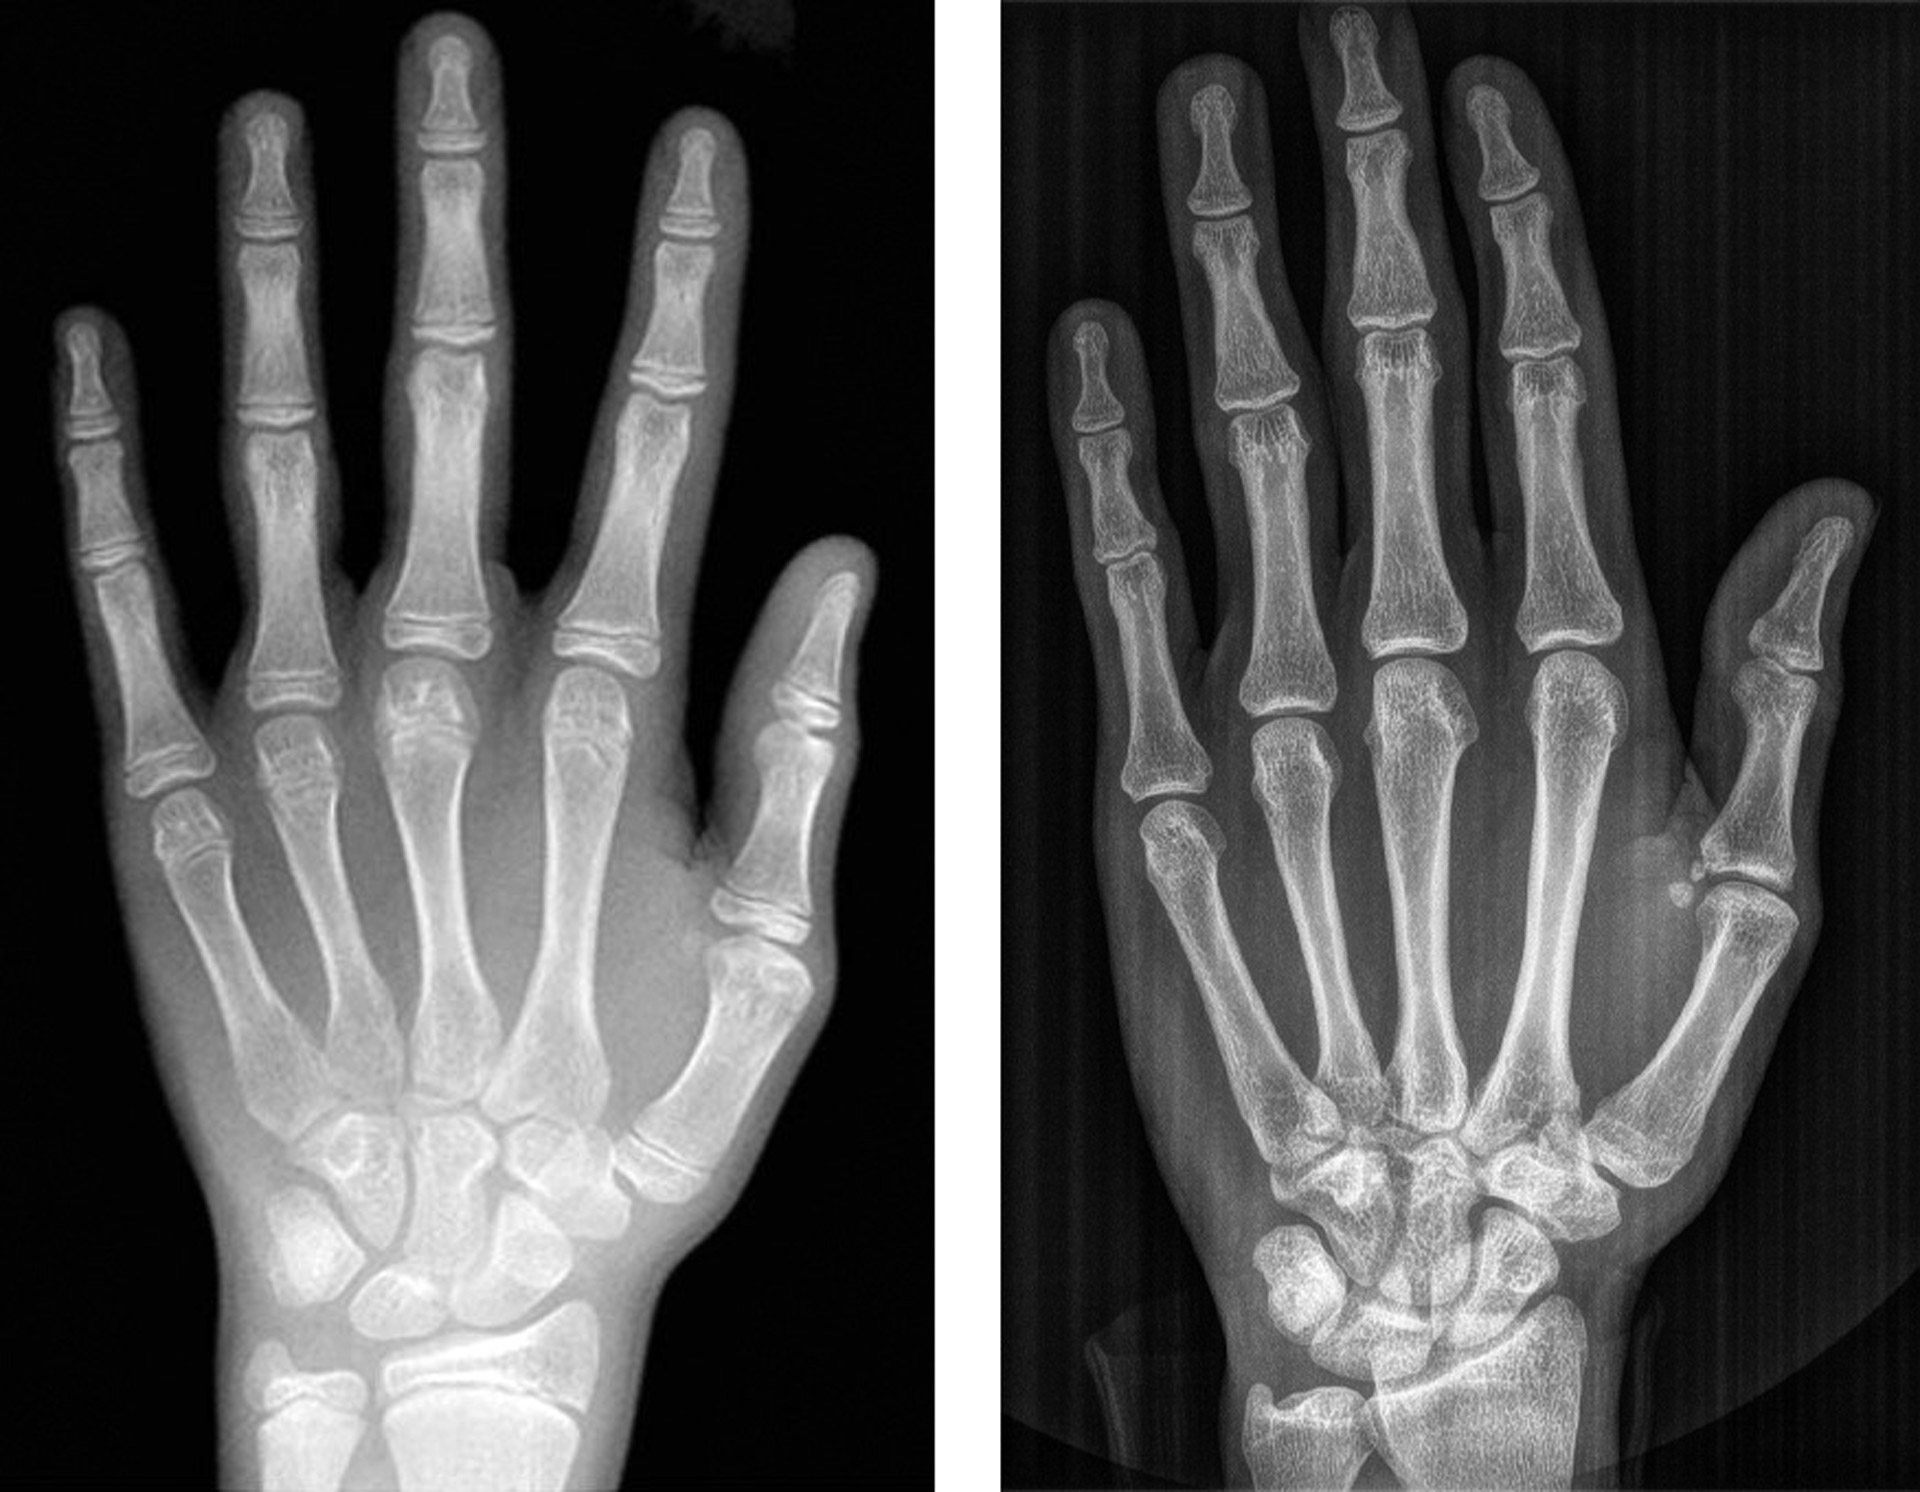

Like dental development is staged, so is bone growth. The most used bones are those in the hand/wrist (figure 4). Like teeth these bones are graded according to an atlas [25]. Teeth and bone develop independently, consequently, it might be a good argument for using both dental and bone development. Research has demonstrated that there is a close correlation between bone and dental age [43]. If bone age and dental age is close it might also be close to chronological age, but if they differ one must look for a reason behind such difference.

Staging whether in bone or teeth is always subjective. BoneXpert is the only automatic and objective grading [39]. Although Norway at present only uses Demirjian’s stages on wisdom teeth the BioAge tables are based on a very large sample from all over the world [7].

Figure 4. According to Greulich and Pyle (25), left: 14 years old boy, right: the epiphyseal lines are obliterated. Male at least 19 years old and female 18.

Two forensic odontologists perform age estimation. A panoramic radiograph and intra-oral radiographs of third molars are analysed according to Liversidge [8], Mincer et al. [22], Kullman et al. [23] and AlQahtani et al. [24]. Skeletal age is estimated from hand and wrist according to Greulich and Pyle [25]. The margin of errors is given by averages and SD of each method. The final results are submitted as to whether it is likely that the applicant is younger than 18 years of age. The applicant benefits from any doubt.

Bone age is assessed by a radiologist using a radiograph of the left hand-wrist and the Greulich and Pyle (GP) Atlas method [25]. Dental age is evaluated through panoramic radiographs, complemented by radiographs of all four third molars. The crown and root development of these molars is analyzed by a forensic odontologist using the 10 stages (C½ - Ac) by Gleiser and Hunt, modified by Köhler [27]. Each of the four third molars contribute one stage. Reference studies by Köhler, Haavikko, and Mincer [22][27][28] are used to determine mean chronological ages for each stage.